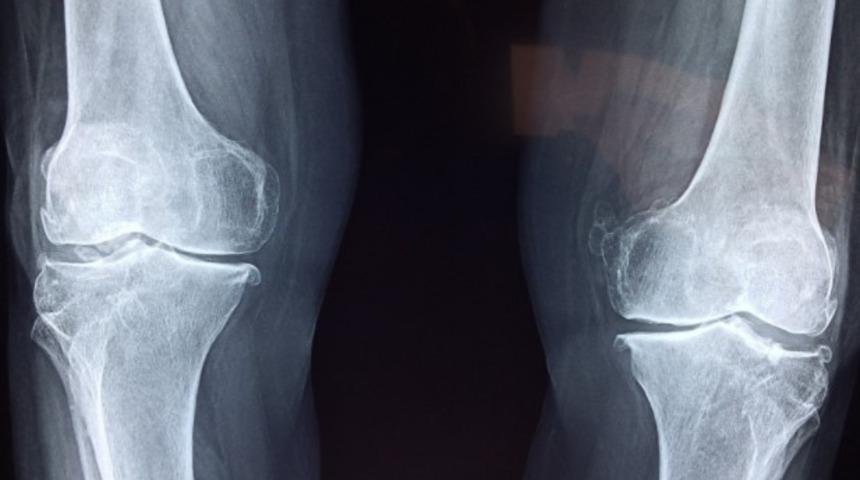

Sinovit nedir diye bakıldığında, vücutta yer alan eklemlerin büyük kısmının iç yüzünü döşeyen zarın yani sinovyumun zarar görmesi yada iltihaplanması sonucunda oluşan bir hastalıktır. Sinovit nedir tıp dünyasında özellikle çocuk hastalıklarında sıkça karşılaşılan bir sorudur. Genellikle çocuklarda görülen bir hastalıktır. Belirgin kalça ve bazen diz ağrısı, topallama ve yürüyüşte aksama gibi etkileri ile çocuklar için ağrılı olabilecek bir süreç olarak değerlendirilir. Çocukların bacaklarına yük vermek istememesi, kalça ve diz hareketlerinde kısıtlılık en belirgin klinik bulgular arasında yer alır. Doktor muayenesi sonrasında yapılan kan testleri öncelikli olarak bir eklem fonksiyonunu ekarte etmek amacıyla istenir. Daha sonra hastadan enfeksiyon parametreleri olan sedimentasyon ve CRP ile tam kan bir kan sayımı istenir.

Radyolojik olarak çekilen kalça ve pelvis grafikleri normal düzeylerdedir. Kalça eklemi içindeki sıvının ne kadar biriktiğini belirlemek için kalça ultrasonu istenebilir. Kan değerlerinde aşırı bir yükseklik olmaması, klinik bulgular ve hastanın dikkatli öyküsünün alınması ve incelenmesi sonucunda sinovit tanısı konulabilir. Hastalık bulguları hastalığın derecesine göre farklılık gösterir. Bu nedenle her hastada bulguların belirlenmesi ve ilerlemesi süreci aynı değildir. Zaman içerisinde sinovit bulguları kendi kendine ilerleyebilir ya da gerileyebilir.

Genellikle çocuklarda görülen sinovit rahatsızlığının belirtileri arasında belirgin kalça ve bazen diz ağrısı, yürürken topallama, aksama çocuğun ağrılı olan bacağa yük vermek istememesi, kalça ve diz hareketlerinde kısıtlılık gibi belirtileri vardır. Aynı zamanda sinovit hastalığına neden olan diğer hastalıklar arasında romatoid artrit, tetik parmak, gut ve septik artrit vardır. Yapılan kan testlerinde öncelikli olarak bir eklem enfeksiyonunun var olup olmadığı belirlenir. Tedavi sürecinde ilk amaç eklem enfeksiyonunu ekarte etmektir. Hastadan enfeksiyon parametreleri, sedimentasyon ve CRP ile tam kan sayımı yapılır. Radyolojik olarak çekilen kalça ve pelvis grafiklerinin normal sınırlarda olmalıdır. Kan değerlerinin ve çekilen radyolojik filmlerin normal olması nedeniyle belirtileri anlayabilmek için hastanın öyküsünün dikkatli bir şekilde dinlenmesi gerekir. En yaygın belirtiler arasında kalça ve diz ağrıları, yürürken topallama, ağrı olan ayağa ağırlık verememe, basamama gibi belirtileri vardır. Sinovit kendi kendini sınırlayan bir rahatsızlık olduğu için çok tehlikeli değildir. Septik artirit denilen bir mikrobiyal kaynaklı bir rahatsızlıktır. Eklem iltihabı ile benzer belirtiler gösteren rahatsızlığın anlaşılabilmesi ve ayrımının iyi yapılması gerekir. Bu nedenle sinovit belirtilerinin aileler tarafından bilinmesi ve çocukların bu belirtilerden en az birini göstermesi durumunda vakit kaybetmeden bir uzmana danışılması gerekir.

Sinovyum içeren ekleme sinovyal eklem adı verilir. Sinovit kemik içinde bulunan bu zarın kalınlaşmasına ve bu nedenle ağrı, şişkinlik, ateşi kızarıklık ve hareket etmede zorluk gibi belirtilere neden olur. Sinovyal eklemler, el ve ayak parmakları, el bileği, ayak bileği, dirsek, siz, omuz ve kalça eklemleridir. Sinovyal eklem çevresinde bulunan tendonlar bazı zamanlarda eklem içine kadar uzanır ve eklem zarı ile bütünleşir. Buna tenosinovya adı verilir. Bu dokunun iltihaplanması ile tenosinovit olarak adlandırılır. Sinovit ve tenosinovir genellikle iltihaplı romatizmal hastalıklar sonrasında ortaya çıkar. Tedavisinde ise dinlenme oldukça önemlidir. Ağrı bulunan eklem bölgesinin dinlendirilmesi ve günde 2’şer saat ara ile 10-15 dakika boyunca soğuk kompres uygulaması yapılır. Tüm bunların yanında ağrı kesici tedavinin önemli bir noktasıdır. İleri düzeylerde ise eklemin hareket etmesini engellemek amacı ile 3-4 günlüğüne ilgili bölüm ateline alınabilir.